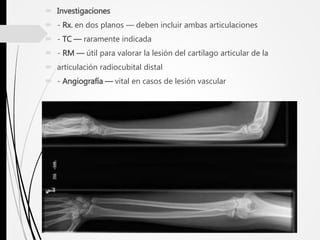

 Investigaciones

 - Rx. en dos planos — deben incluir ambas articulaciones

 - TC — raramente indicada

 - RM — útil para valorar la lesión del cartílago articular de la

 articulación radiocubital distal

 - Angiografía — vital en casos de lesión vascular

 Investigaciones  -Rx. en dos planos — deben incluir ambas articulaciones  - TC — raramente indicada  - RM — útil para valorar la lesión del cartílago articular de la  articulación radiocubital distal  - Angiografía — vital en casos de lesión vascular